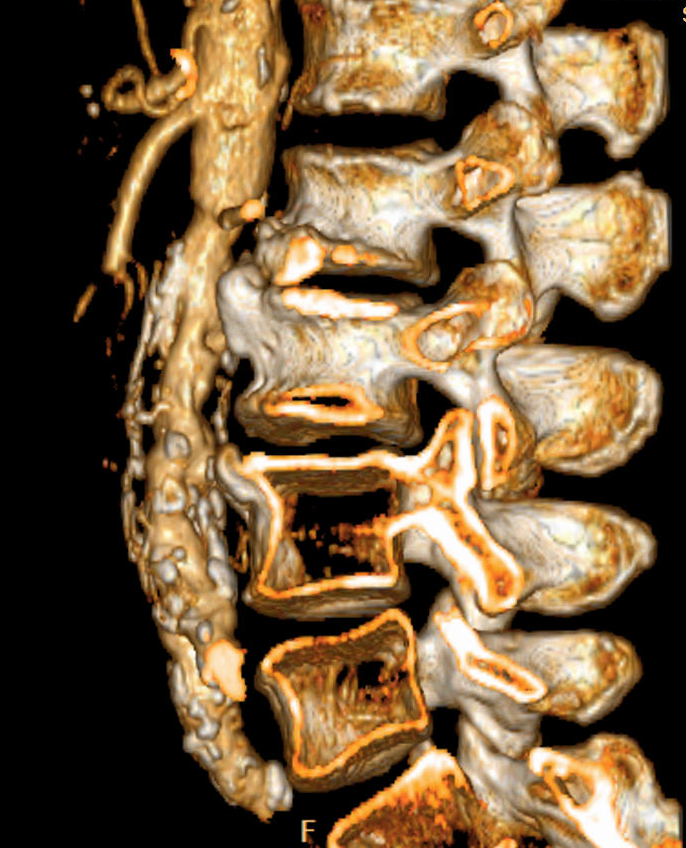

15.2.2.1. In spine trauma

Conventional X-ray exmination is still the primary imaging modality in cases of smaller traumas where clinical symptoms suggest that the damage is mostly affecting the paravertebral soft tissues. In the setting of polytrauma, checking for spinal injuries on the CT scan is part of the image evalutaion.

During evaluation the cervical spine needs to be examined the most urgently which allows us to decide whether the cervical collar is safe to be removed or if it is safe to intubate the patient using the regular method of hyperextension of the neck (e.g. when preparing for urgent surgery). We need to pay extra attention to the possible dissection of the vertebral arteries as they are running between bony structures!

When examining the spine, it is important to decide that the injury is stable or unstable. AO classification of fractures should be used avoid miscommunication. This includes the evaluation of the intervertebral discs and the ligaments which are better appreciated with an MR study and provide extra information for surgical planning. MR studies are also necessary in cases where the CT scan cannot explain acute neurological symptoms because the state of the myelon, traumatic disc herniation and intraspinal haematomas can be only detected with MR.